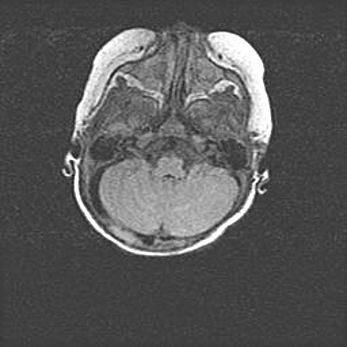

Мальформация Денди-Уокера. Киста задней черепной ямки.

Агенезия мозолистого тела.

Возраст: 2,5 месяца

Вес: 2420 г

Пол: женский

Окружность головы: 37 см

Срок гестации: 32 недели

Мальформация Денди—Уокера — редкий вид патологии ЦНС, представляющий собой врожденный порок развития каудального отдела ствола и червя мозжечка, ведущий к неполному раскрытию срединной (Мажанди) и латеральных (Лушка) апертур IV желудочка мозга. Для этогно синдрома характерна триада симптомов: гипотрофия червя мозжечка и/или полушарий мозжечка, кисты задней черепной ямки, гидроцефалия различной степени. В 70% случаев порок сочетается и с другими аномалиями головного мозга, в частности с агенезией мозолистого тела.